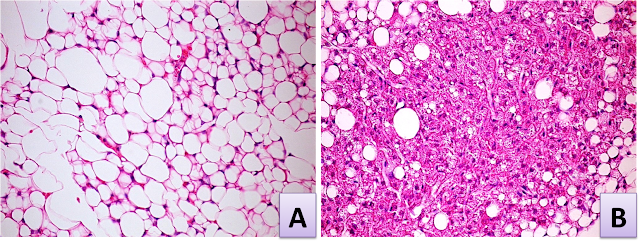

TEJIDOS. ADIPOSO

Indica en el paréntesis, con la letra correspondiente, el tipo de tejido adiposo al que se refiera cada enunciado.

( ) Desaparece posnatalmente

( ) Tiene una distribución particular dependiendo del sexo

( ) En sus células hay más mitocondrias

( ) Se denomina grasa parda

( ) Se denomina grasa blanca

( ) Es unilocular

( ) Es multilocular

( ) Aísla del frío

( ) Genera calor

( ) Tiene receptores para la insulina

( ) Tiene termogeninas en sus mitocondrias

( ) Se sitúa alrededor de los vasos